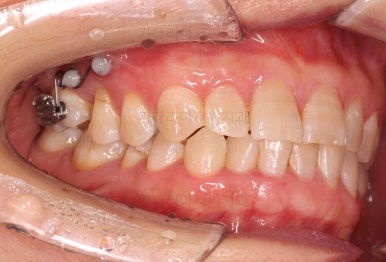

초진 때의 사진입니다.

전반적으로 치열이 삐뚤하고 불균일한 양상이긴 하지만 꼭 이런 부분들까지 교정해야 하는 건 아니에요.

치열에 대한 본인의 개선 의사가 있다면 전반적인 교정을 해줄 필요가 있지만, 그렇지 않다면 굳이 할 필요가 없는거죠.

제일 하단의 X-ray에서 문제점이 보이는데요.

해당 부분의 어금니 1개가 없었어요.

어금니가 없어진지 꽤 시간이 흘렀기 때문에 몇 가지 문제점이 나타나는데요.